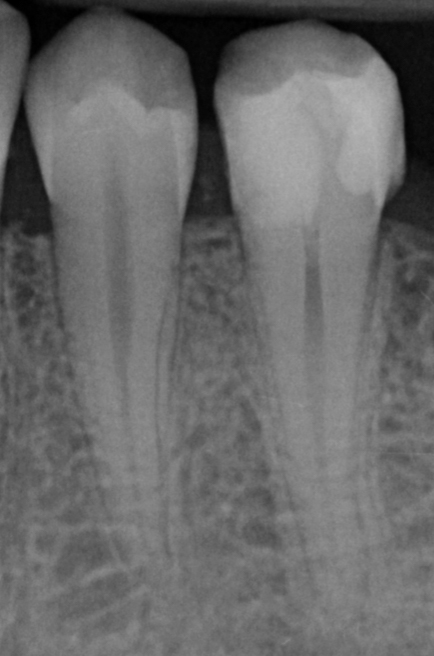

De cursus bestaat uit een combinatie van interactieve theorie en praktische oefeningen. Er wordt gewerkt met preparatiemodellen waarin een diepe caviteit en pulpablootstelling wordt gesimuleerd.

• Preparatie van diepe caviteiten in molaren;

• De anatomie van het pulpadak en pulpakamer correct te herkennen en prepareren;